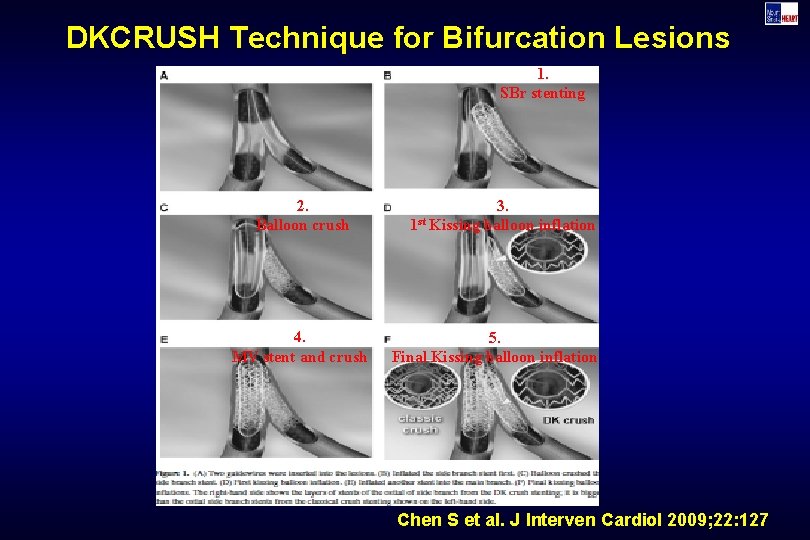

DKCRUSH Technique for Bifurcation Lesions 1. SBr stenting 2. Balloon crush 4. MV stent and crush 3. 1 st Kissing balloon inflation 5. Final Kissing balloon inflation Chen S et al. J Interven Cardiol 2009; 22: 127